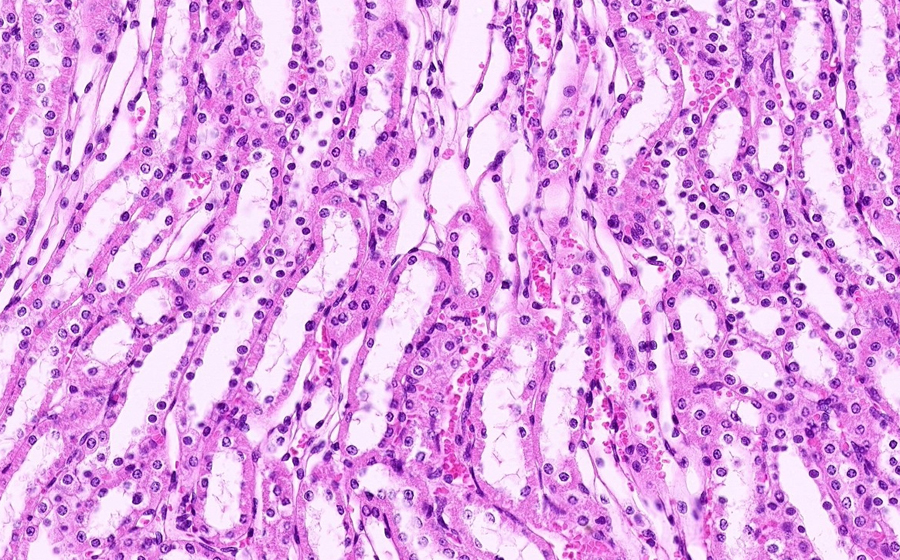

Slide 3: Glomerulonephritis - chronic

Histologic section of kidney from a patient with chronic glomerulonephritis. (click here to review normal tissue)

Image 2 - 12.5X

Slide 3 - Image 2